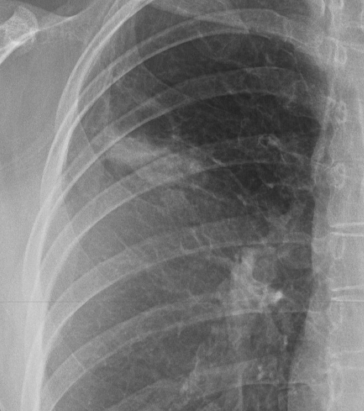

Syndrome Alvéolaire

- Condensations

- Bronchogramme aérique